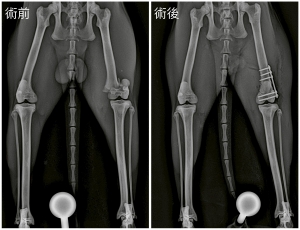

X光檢查顯示是股骨遠端生長板骨折,屬於Salter-Harris 第二型生長板骨折

米魯接受了骨板固定手術,骨折對位固定之後,貓貓很快就可以恢復行走功能,一個半月後再次拍攝 X 光就可以看到骨折處已經完全癒合啦